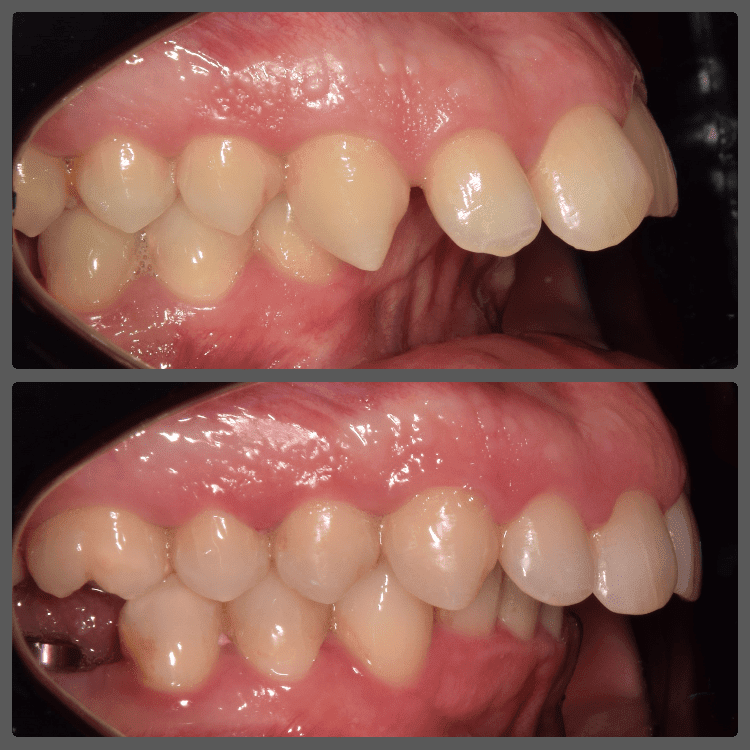

Bálint a 90 fokban elfordult jobb felső kismetszője miatt keresett meg engem. A vizsgálatokat követően kiderült, hogy a probléma ennél jóval komplexebb: súlyos keresztharapást, súlyos mélyharapást és felső rágósík billenést diagnosztizáltam nála. Alsó-felső H4 önligírozó fogszabályozó készülék, intermaxilláris gumihúzás és elülső harapásemelők segítségével korrigáltuk az eltéréseket. A bal oldali rágósík billenést fogszabályzási miniimplantátum alkalmazásával oldottuk meg. A bal felső-elülső fogakat felfelé mozgattuk, a miniimplantátumhoz húzva. Bálint esete igen komplex volt, ám kiváló együttműködésének köszönhetően 26 hónap alatt végeztünk a kezelésével (beleértve a 2-3 hónapos COVID-19 miatti leállást is). Az eredmény úgy gondolom magáért beszél!